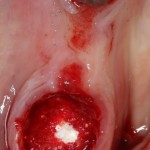

Гранулема настолько большая, что ее видно из лунки:

Аккуратно ее удаляем. Приходится пожертвовать межкорневой перегородкой:

В лунку помещаем Neocones, Bioss Collagen:

Затем к краям лунки подшивается Mucograft Seal: